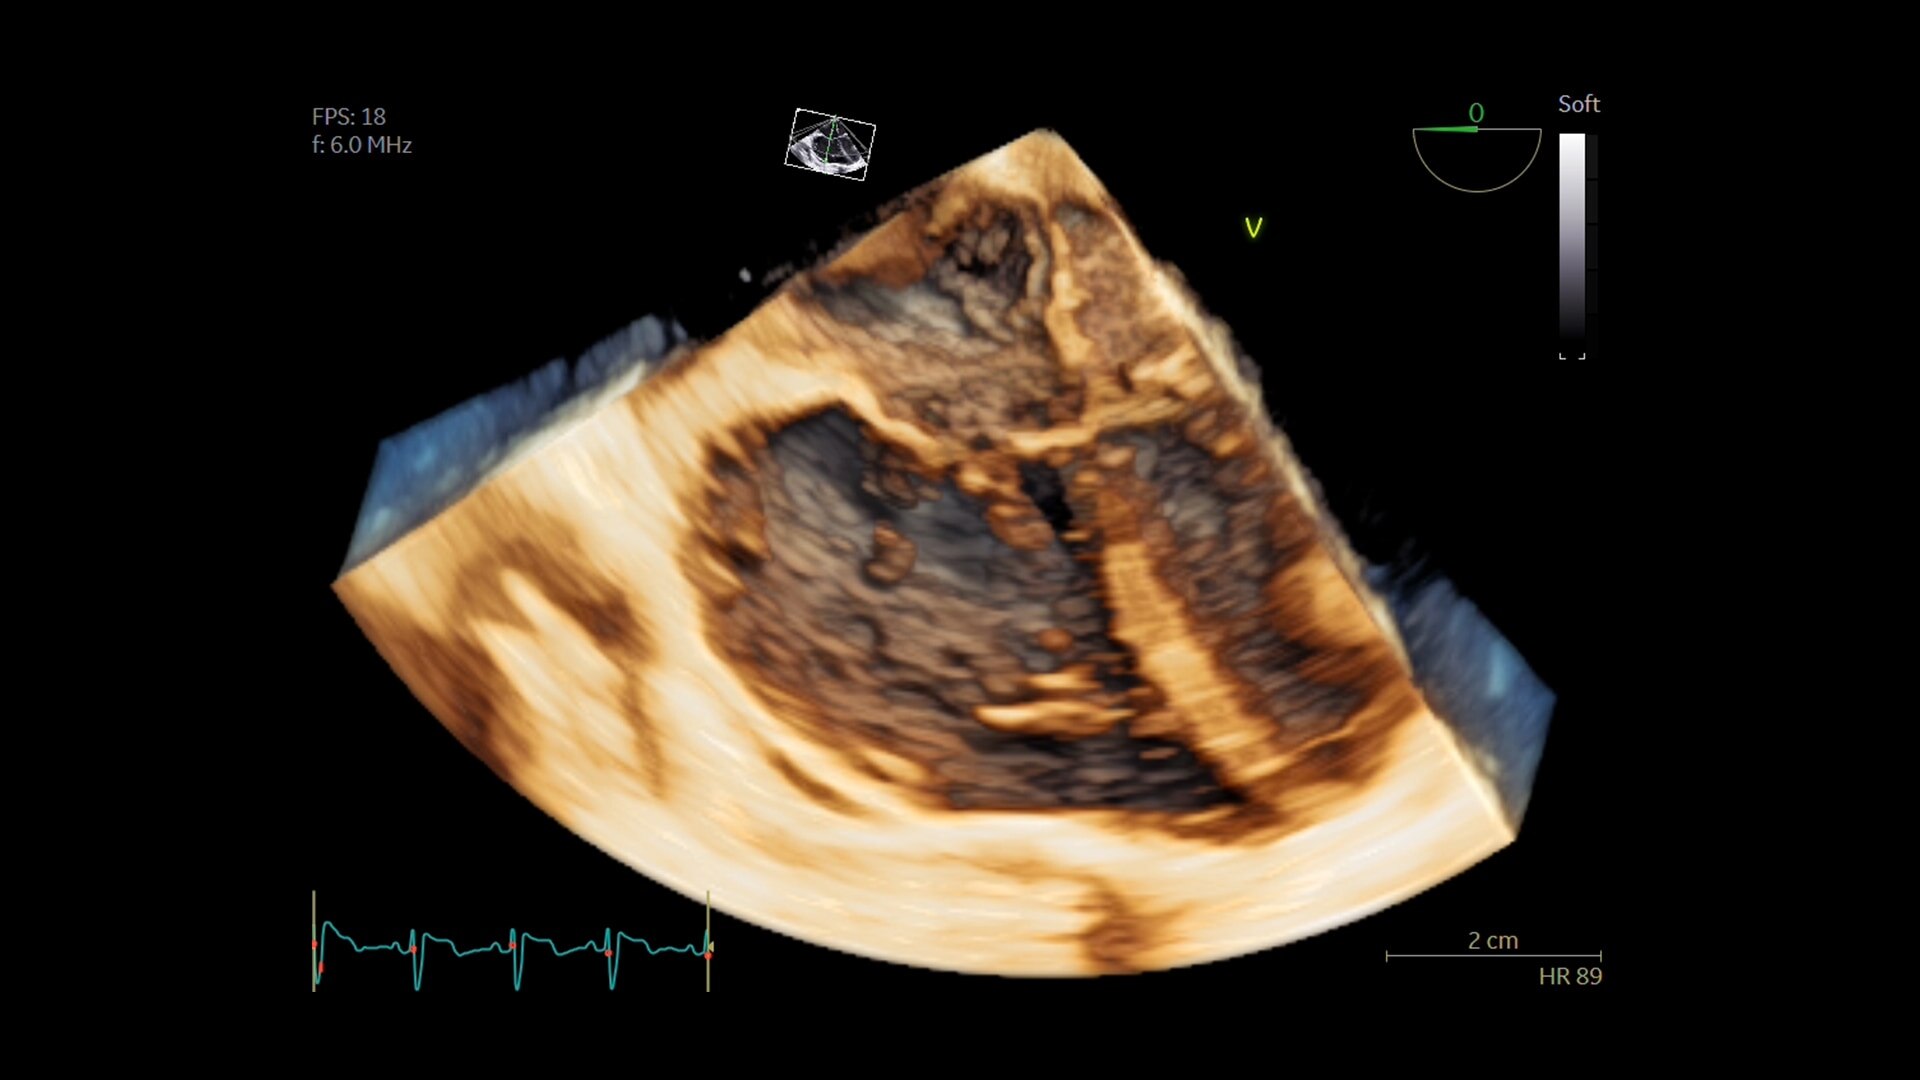

SIGNA™ Champion offre un design modulare con opzioni software e hardware pronte per soddisfare le priorità cliniche. Include strumenti di base e avanzati e soluzioni per la qualità delle immagini come AIR™ Recon DL e Sonic DL™. Queste applicazioni consentono non solo di ottimizzare i casi di routine, ma anche di operare in altri campi specifici come neurologia, apparato muscolo-scheletrico, cardiologia e oncologia. E non è tutto. SIGNA™ Champion è in grado di offrire configurazioni a 32, 48 e 64 canali per garantire la massima flessibilità e semplificare la configurazione delle bobine sulla base delle diverse anatomie.

AIR™ Recon DL potenzia le funzionalità della tua RM offrendo una qualità dell'immagine superiore con tempi di scansione ridotti.